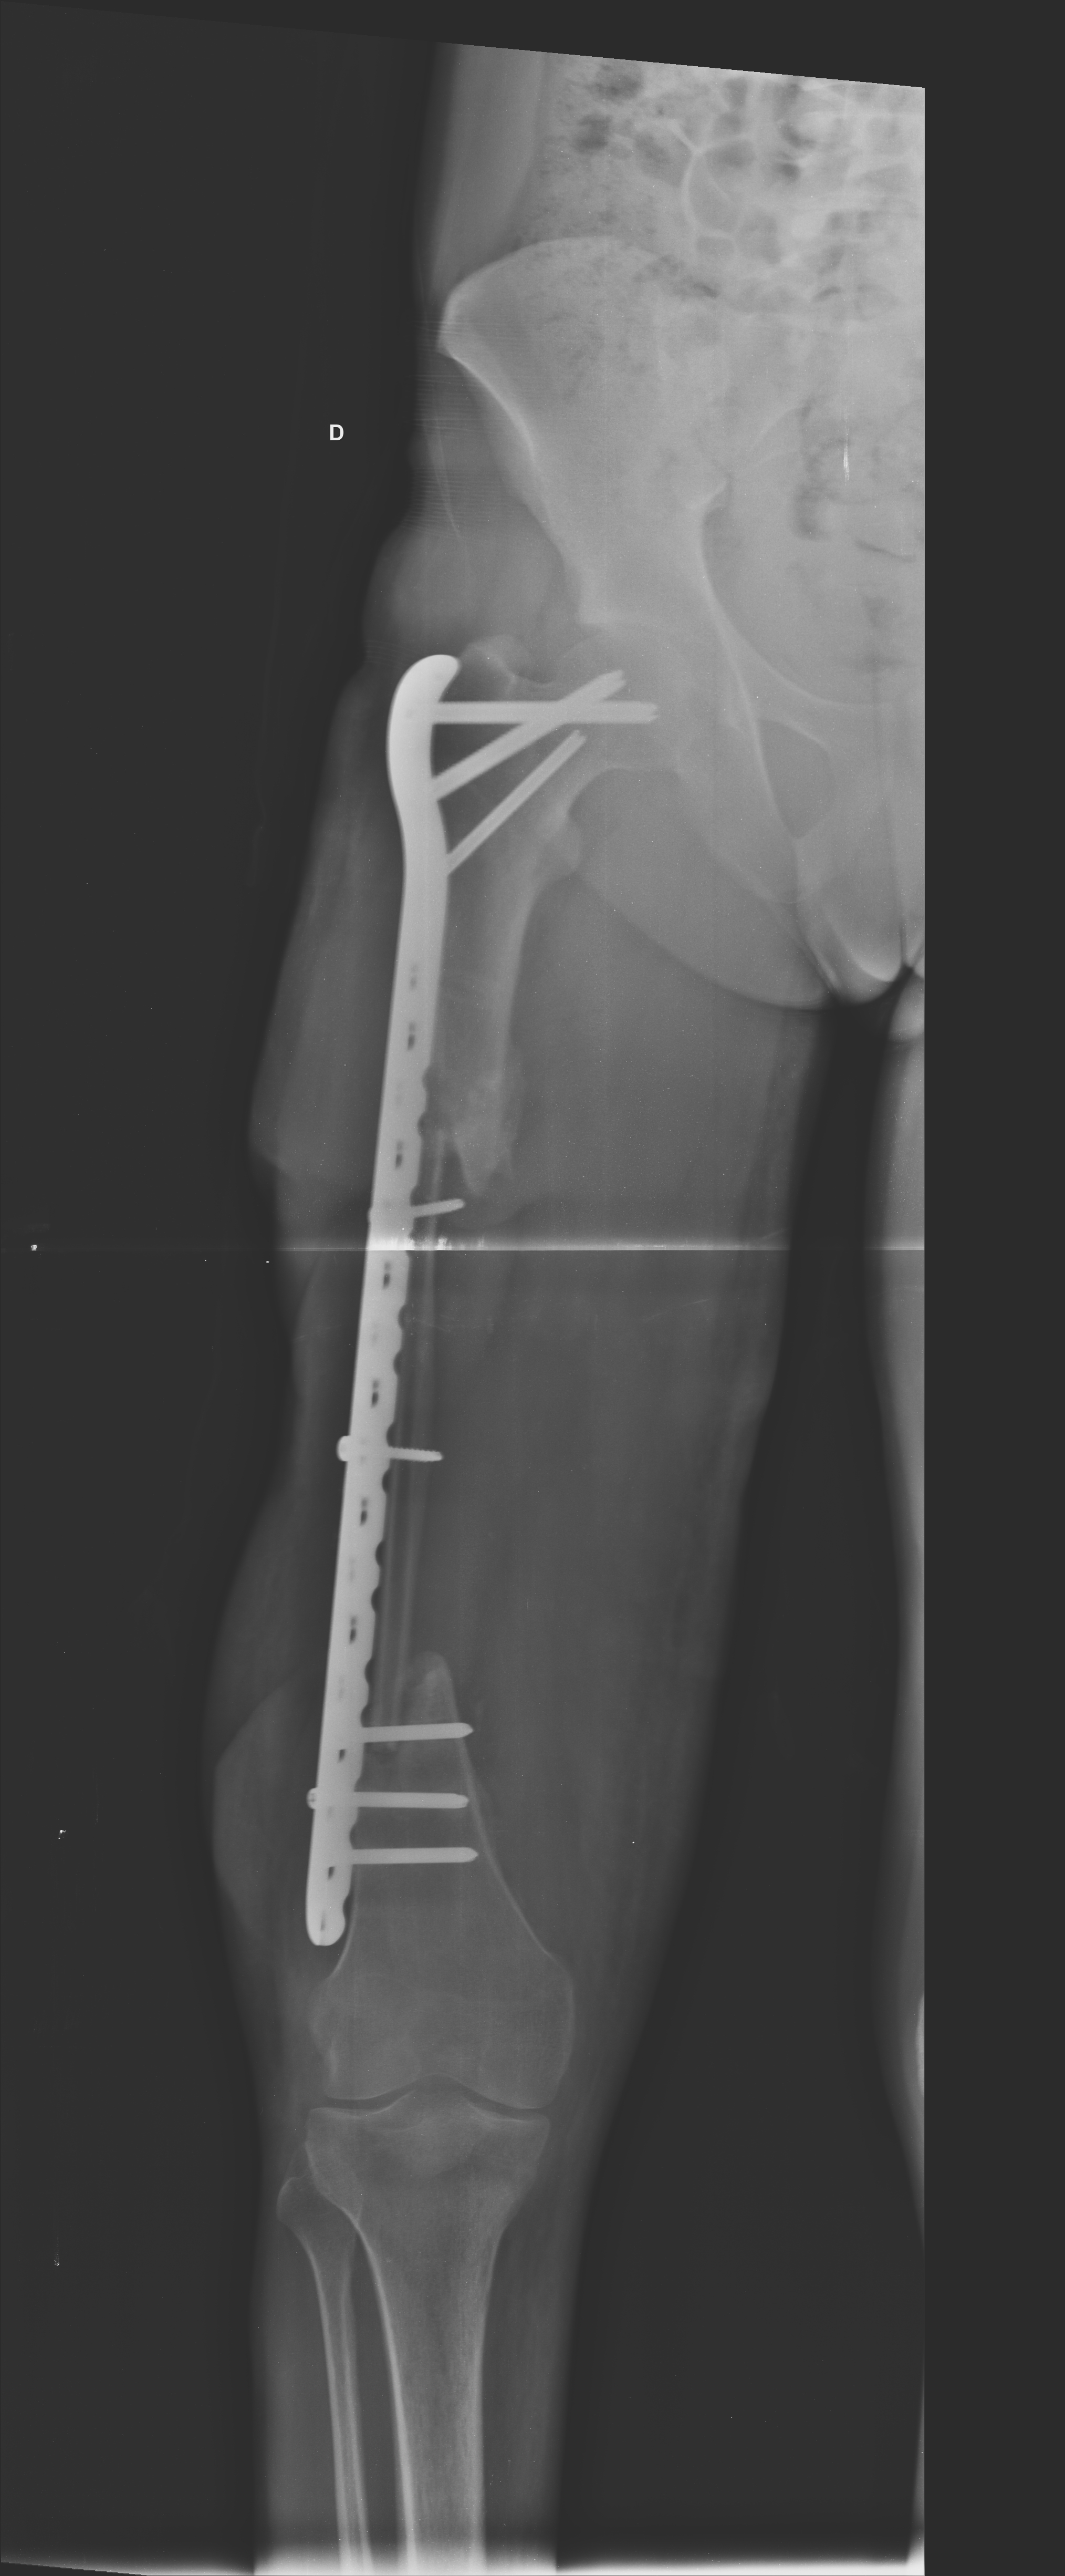

Neste estudo, os pacientes sofreram traumas graves, com perdas ósseas e de partes moles, realizaram múltiplas cirurgias e tiveram longos períodos de reabilitação, e apesar de tudo isso alcançaram bons resultados. Acredita-se que este resultado também esteja relacionado com o início precoce do programa de reabilitação. No paciente que apresentou melhor resultado (Figura 1), observou-se consolidação óssea, com hipertrofia significativa da fíbula, amplitude de movimento da articulação do joelho em 110° e marcha com uso de bengala para meio externo, devido a sua insuficiência do mecanismo extensor do joelho. Portanto, atingiu uma recuperação funcional adequada, onde consegue realizar atividades como subir e descer escadas sem dificuldades e conseguiu retornar ao mercado de trabalho.

Figura 1 - Radiografia de um dos pacientes do estudo. a: raio-x inicial com fratura de fêmur. b: fíbula vascularizada implantada 1 ano após o trauma. c: 6 anos após a fíbula vascularizada com consolidação óssea evidente